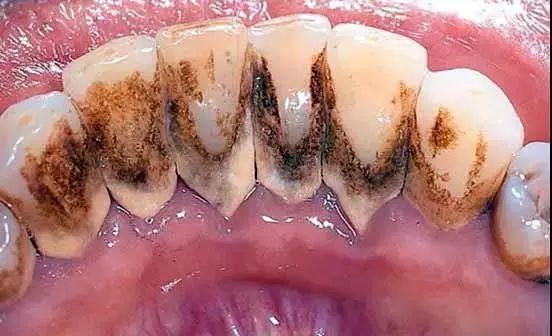

如果更严重点,有可能是这样的↓↓↓

牙龈周边积聚着大量黑褐色牙结石并伴有口腔异味,牙龈红肿明显,时间一长,很有可能造成牙齿松动脱落。

如下图↓↓↓

我们的口腔每天都处在水深火热中...在我们大快朵颐之后,若不注意口腔卫生,长期下来就会堆积很多黄色的,棕色的甚至黑色的脏东西,也就是牙结石。